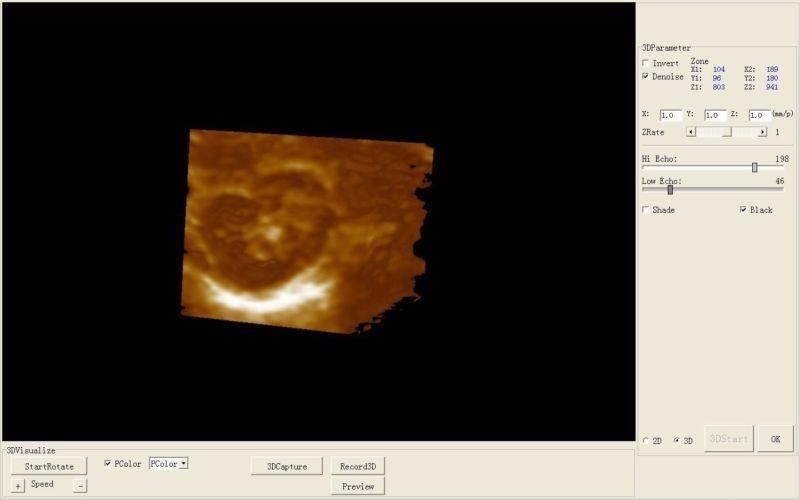

3D Ultrasound Capabilities

The integration of 3D imaging technology in the Laptop Ultrasound scanner transforms the diagnostic experience. This feature not only enhances image clarity but also provides a comprehensive view of anatomical structures, making diagnosis more reliable. Doctors can identify issues earlier and more accurately because they can see three-dimensional representations of organs. This capability is particularly important in prenatal care and gynecological assessments, ensuring better health outcomes for patients.